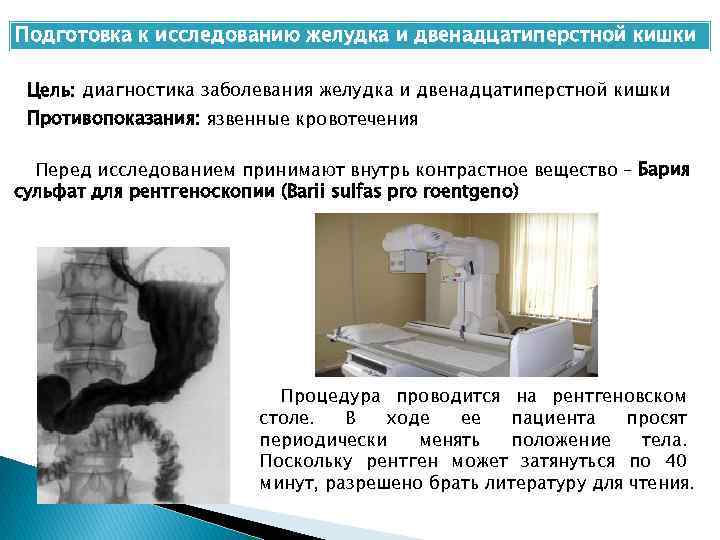

Процедура рентгенологического исследования

Рентгенологическое исследование

X-ray examination of the esophagus ©